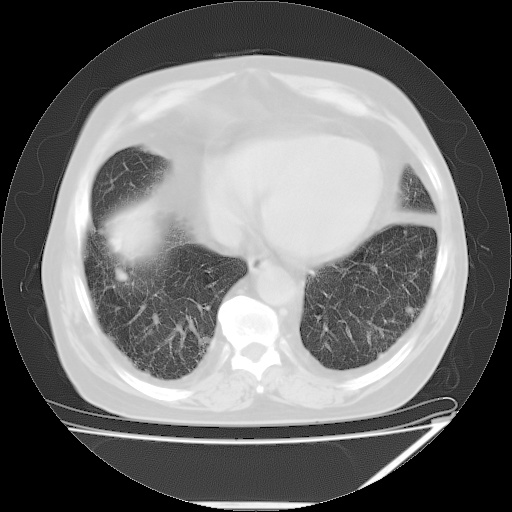

患者,男51岁,反复咳嗽多年,加重10余天,自觉精神不振,无发热,无尿频、尿急及排尿不畅,最近体重有减轻(具体不祥),化验:血常规正常,血糖正常,转氨酶不高,乳酸脱氢酶轻度增高(具体记不得了)

双肺多发结节影,以肺周围分布较多,纵隔淋巴结肿大,考虑双肺转移瘤可能性大。

双肺多发结节影及纵隔内可见肿大淋巴结考虑双肺及纵隔淋巴结转移,建议进一步检查原发灶

1.双肺散在分布小结节影 气管旁淋巴结肿大 中叶背部有胸膜增厚胸膜反应 双侧胸腔积液 考虑转移性肺癌

本例的特点:结节弥漫多发,但所有的结节都没有一个比较清楚的境界,其边界都比较模糊;

其分布并不像转移瘤那样主要分布于肺的外围,而是中心部位较外围的要多;

印象:把炎症性病变放在首位;

考虑 1、慢支并感染; 2、转移待排----右下肺那个有小泡的要小心一些;

建议正规抗炎两周后复查;如有条件请查肿瘤系列;